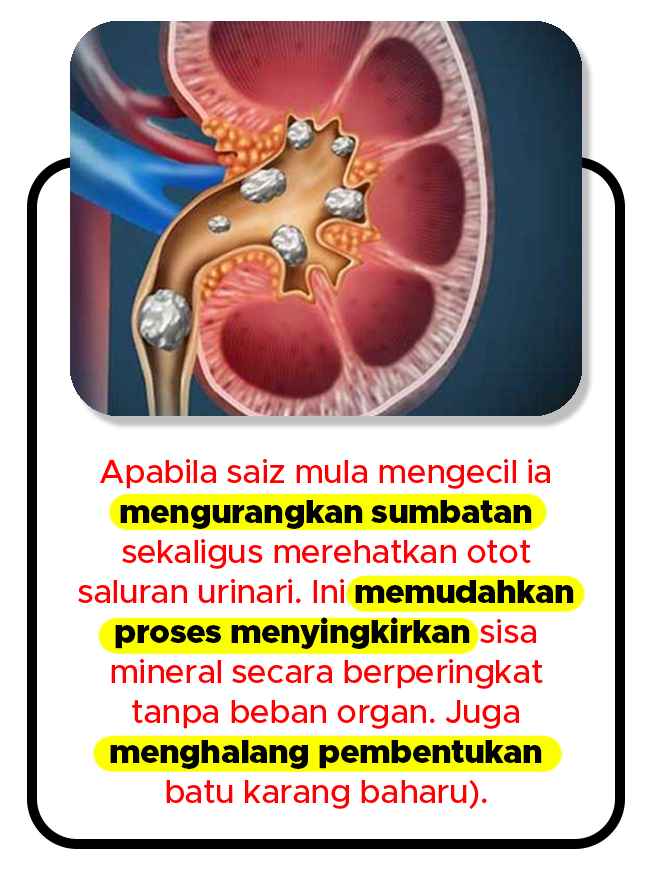

SALUR LANCAR DAN PROSES PENYINGKIRAN 7X CEPAT

Gambar Rajah Fungsi Urix360